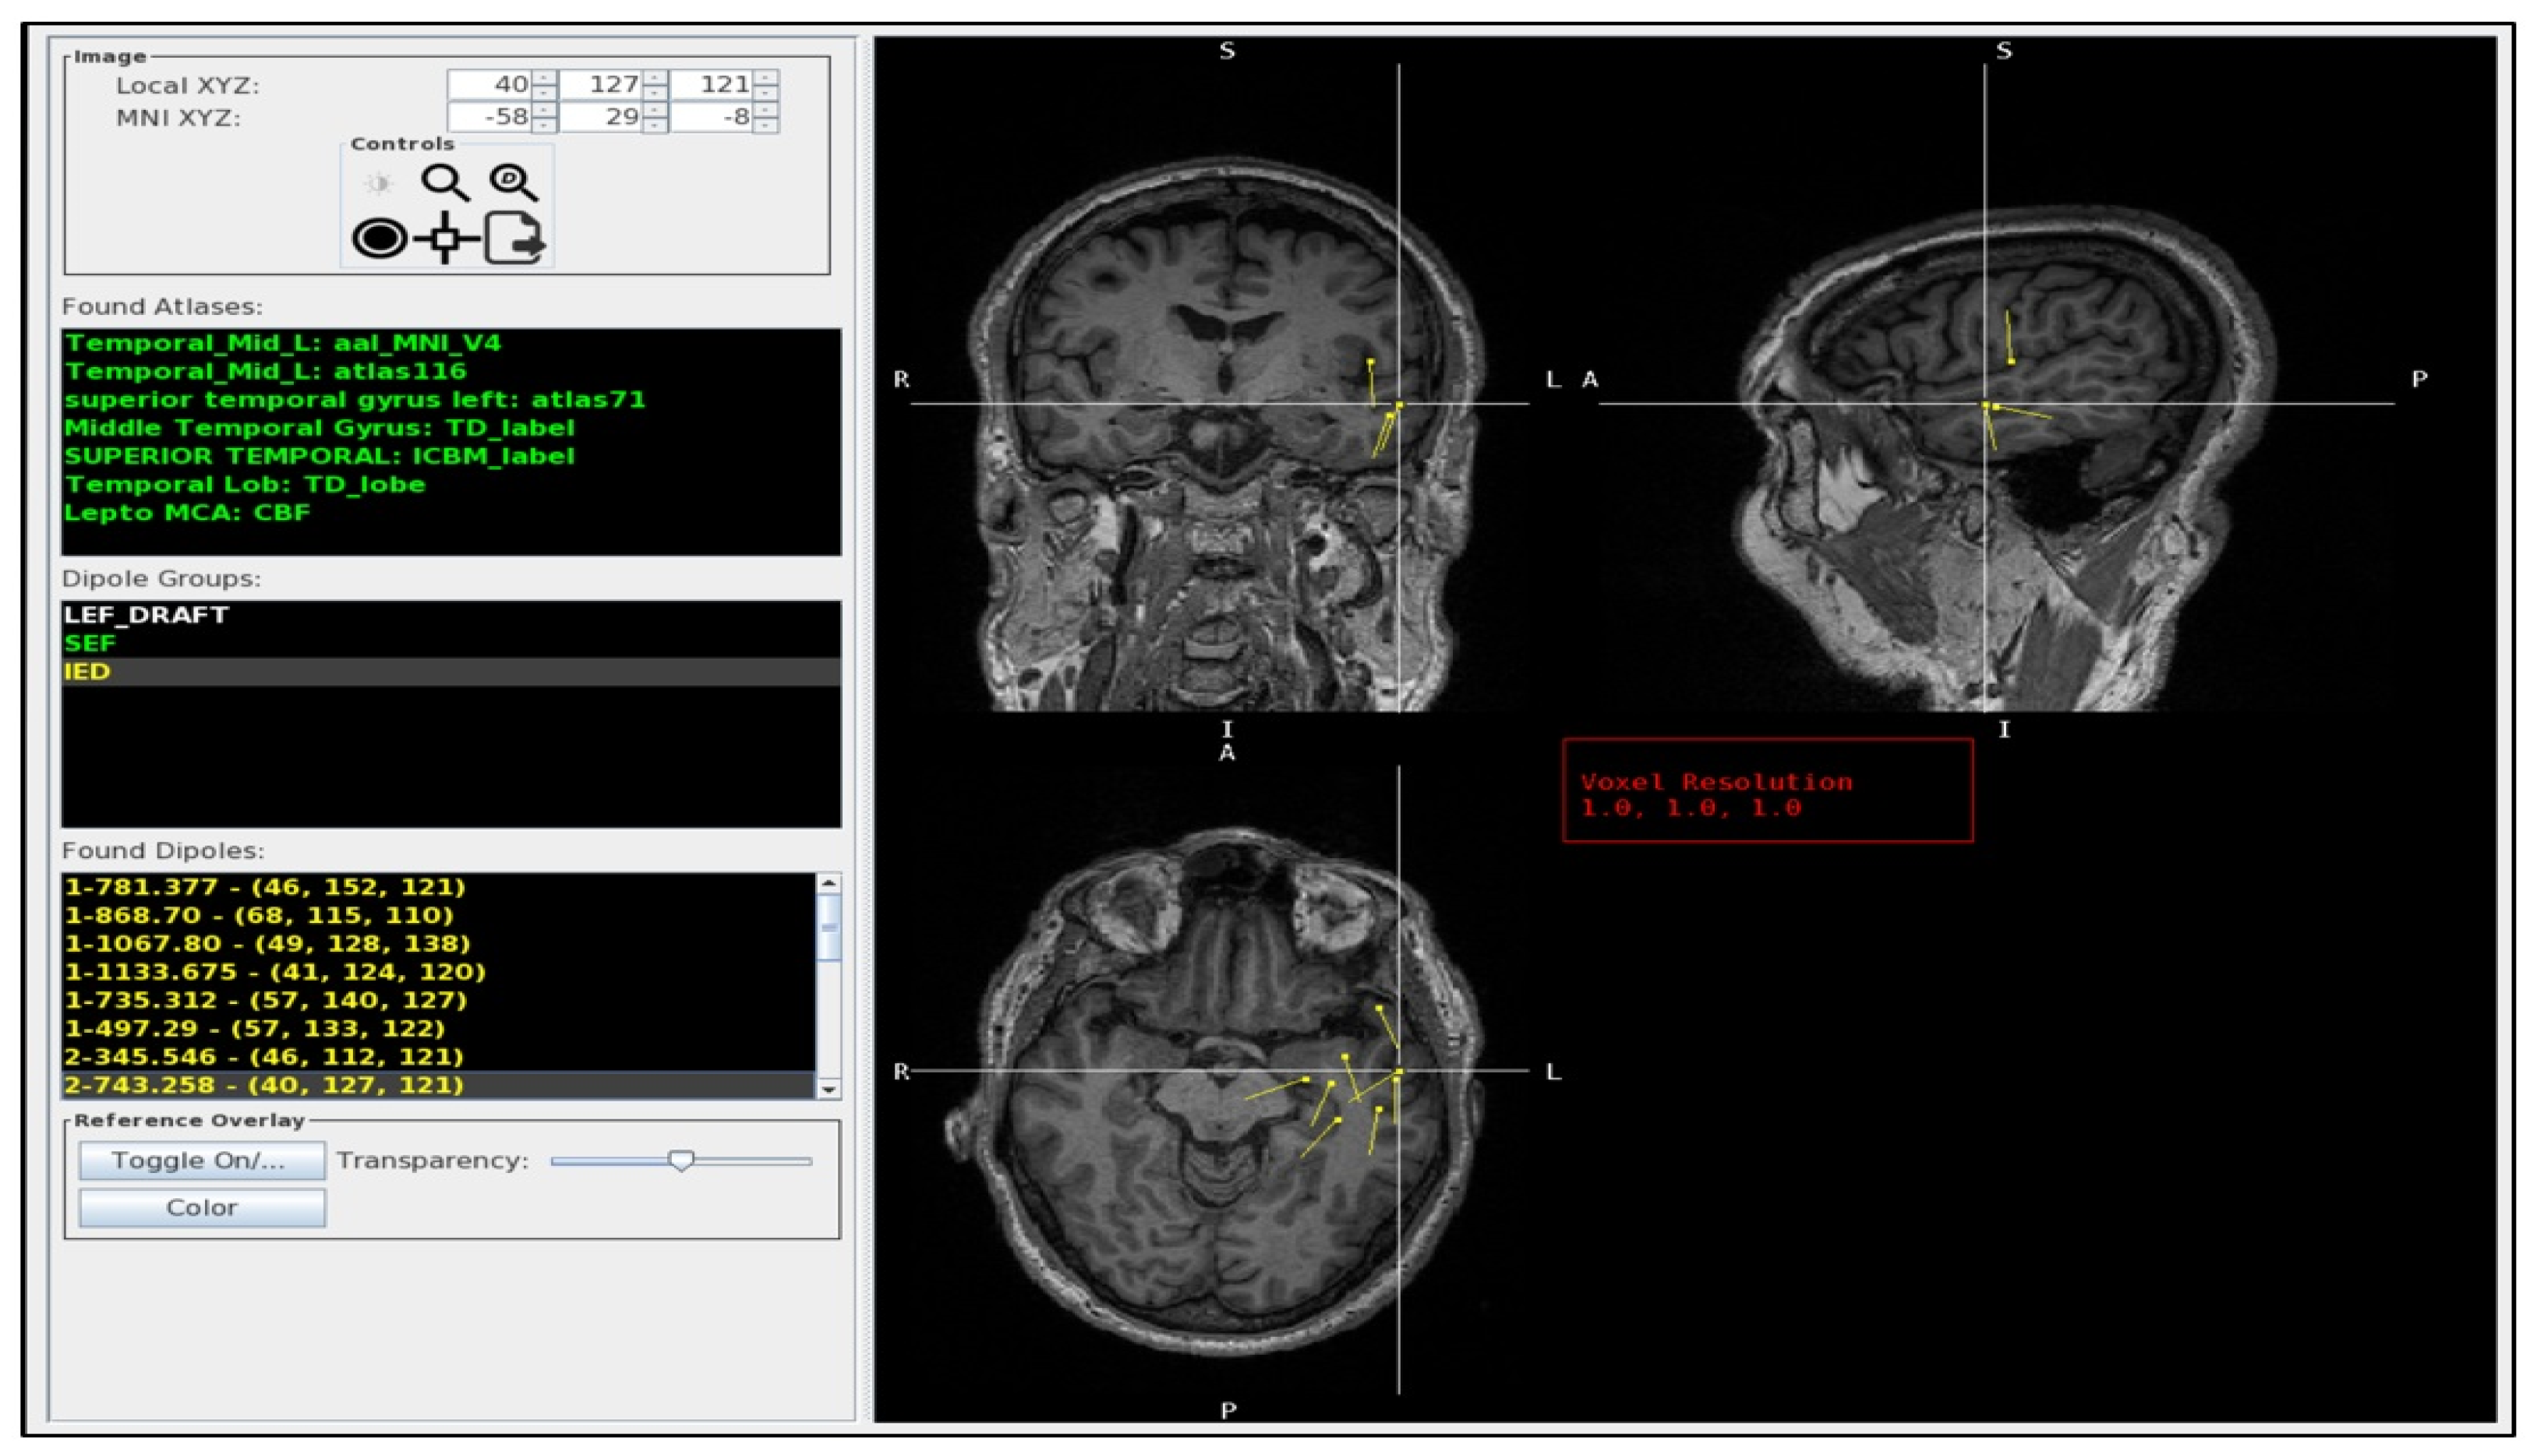

3.1. Usage of the Program Tools